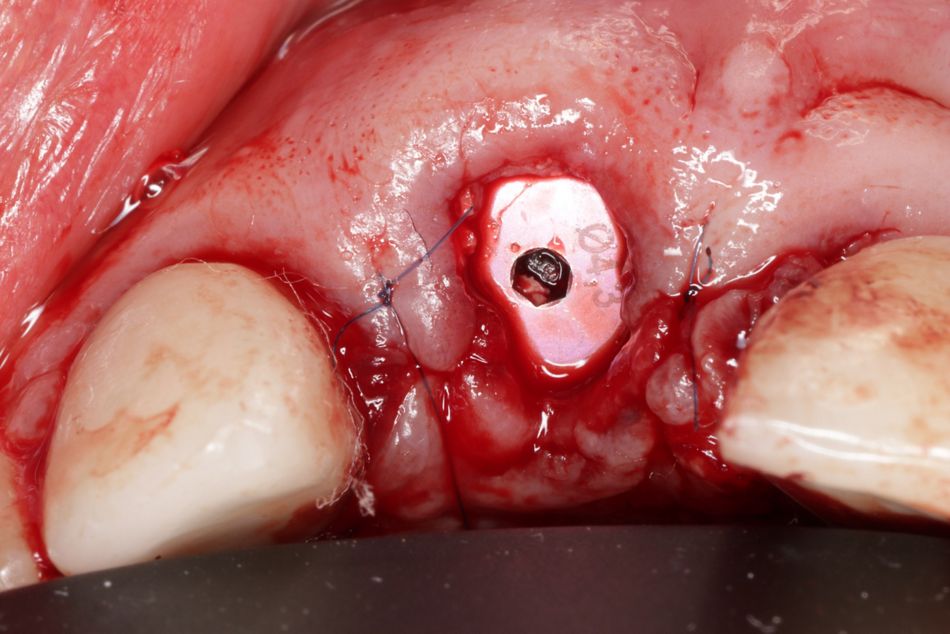

Verwendet wurde im vorliegenden Fall das Implantatsystem Procone (Medentika). Die Aufbereitung des Implantatbettes regio 11 erfolgte nach Bohrprotokoll bis zum Durchmesser 4,3 mm. Der Spalt zum fazialen Knochen wurde mit einem bovinen Augmentat (Cerabone, Straumann) gefüllt. Zur verbesserten Wundheilung sind sowohl das Implantat als auch das Cerabone vor dem Einsetzen mit patienteneigenem Blutplasma bzw. Wachstumsfaktoren (iPRF) benetzt worden (Abb. 7 und 8). Das Implantat wurde nach dem Gewindeschneiden palatinal orientiert inseriert, sodass der Einbringpfosten bukkal hinter der fazialen Fläche der Nachbarzähne platziert war. Der Verschluss erfolgte erstmal mit einer Einheilkappe (Höhe 2 mm) (Abb. 9).

Für ein optimales Weichgewebemanagement und eine adäquate Rot-Weiß-Ästhetik sollte die keratinisierte periimplantäre Mukosa chirurgisch erhalten werden. Hierfür wurden aus dem hinteren Gaumenbereich zwei freie Schleimhauttransplantate (FST) entnommen (Abb. 10) und auf einer Glasplatte mit dem Skalpell entepithelisiert. Die Spenderregion ist mit einem Histoacryl-Kleber primär verschlossen worden. Die entsprechend vorbereiteten Transplantate wurden bukkal und oberhalb der Insertionsstelle hier als Punch mit Einzelknopfnähten (07 Seralene) vernäht und so das gingivale Gewebe maximal gestützt und erhalten werden (Abb. 11).